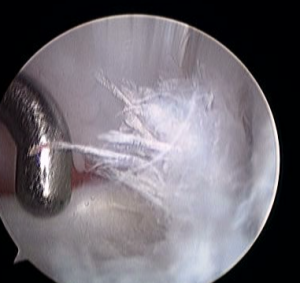

(右)チワワ 2kg

前十字靭帯の完全断裂 靭帯の断端が切れて”ささくれ”ていました。左横に関節内の調べるための器具がみえています